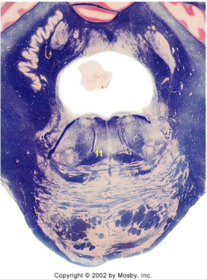

| Nucleus gracilis | |

| Nucleus cuneatus | |

| Fasciculus gracilis | |

| Fasciculus cuneatus | |

| Internal acruate fibers | |

| Lateral (external/accessory) cuneate nucleus | |

| Medullary pyramids | |

| Hypoglossal nucleus | |

| Hypoglossal nerve | |

| Dorsal motor nucleus of X | |

| Nucleus ambiguus | |

| Solitary tract | |

| Solitary nucleus | |

| ALS | |

| Medial lemniscus | |

| Medial longitudinal fasciculus | |

| Spinal tract of V | |

| Spinal nucleus of V | |

| Lateral (external, accessory) cuneate nucleus | |